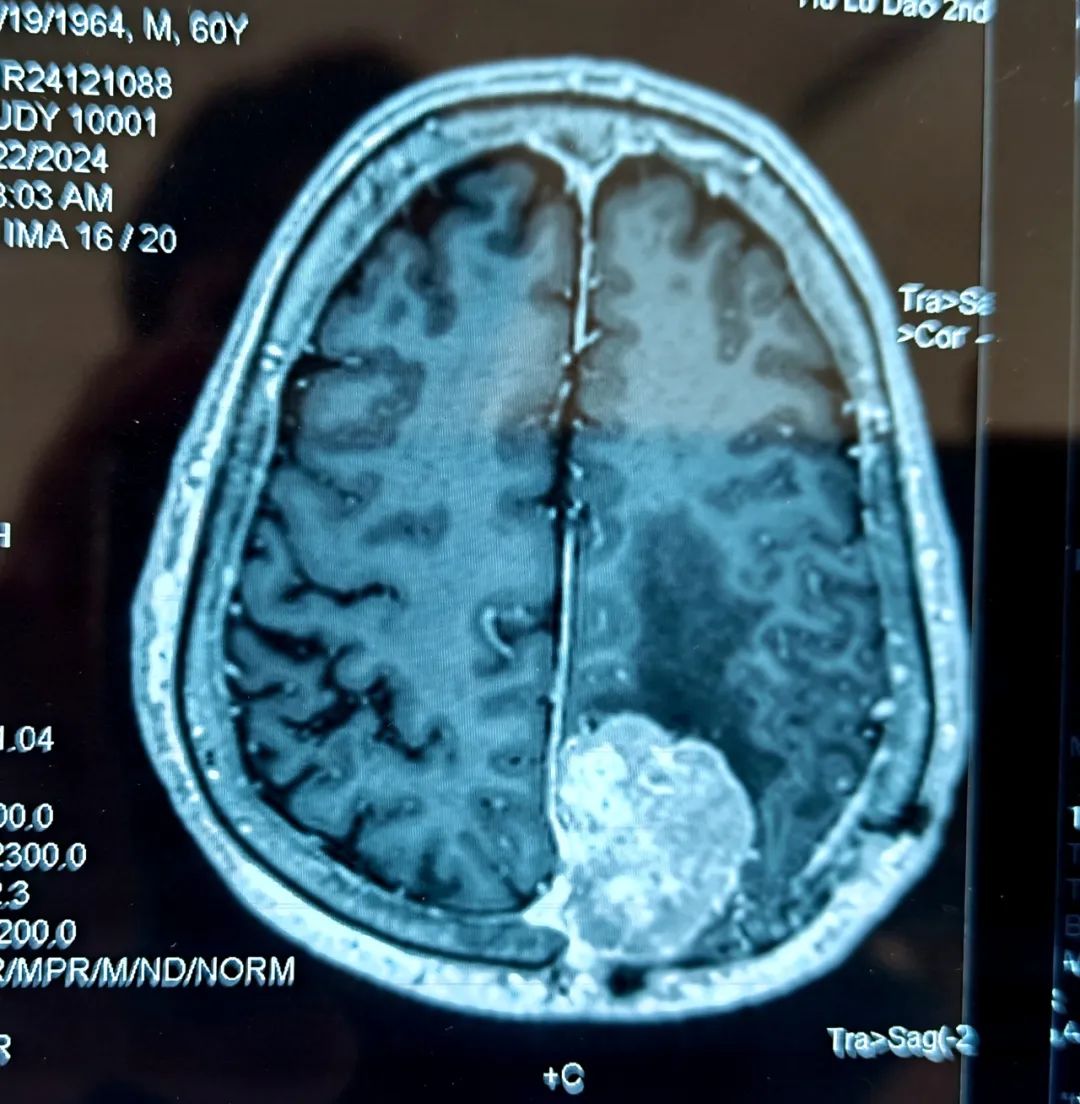

经过团队成员的共同努力,手术顺利完成,患者安返病房。术后在神经外科护理团队的精心护理下,患者病情恢复良好,言语及四肢功能无任何障碍,术后一周便可行走自如。

- 患者术后核磁 -